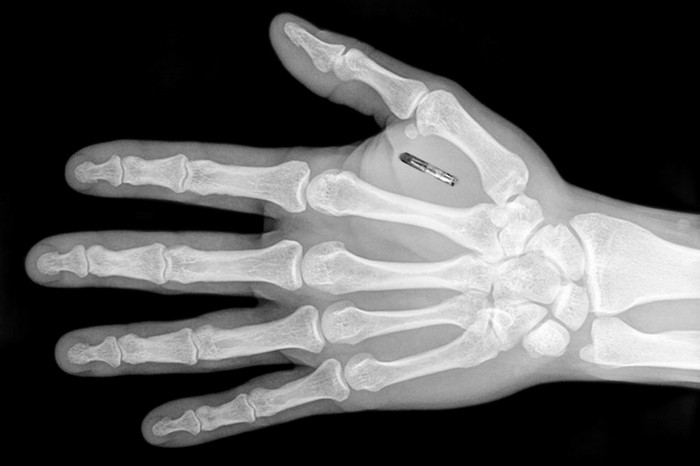

Имплантат вместо пропуска

Шведская технологическая компания Epicenter решила отказаться в своем офисе от традиционных пластиковых пропусков. Она начала постепенно заменять их небольшими имплантатами – RFID-чипами размером с рисовое зернышко. Сотрудникам Epicenter загоняют эти девайсы под кожу кисти правой или левой руки.

Эти микрочипы позволяют сотрудникам Epicenter получить доступ к большому количеству возможностей внутри офиса компании в соответствии с уровнем доступа. Они открывают двери с электронными замками, активируют компьютеры, ксероксы и другую офисную технику, фиксируют время пребывания человека на работе и т.д.

При этом внедрение такого чипа не является обязательным условием работы в компании Epicenter. Однако всего за два месяца более половины сотрудников решились на подобный шаг – это удобно и революционно. Многие хотят стать участником уникального пока что эксперимента.